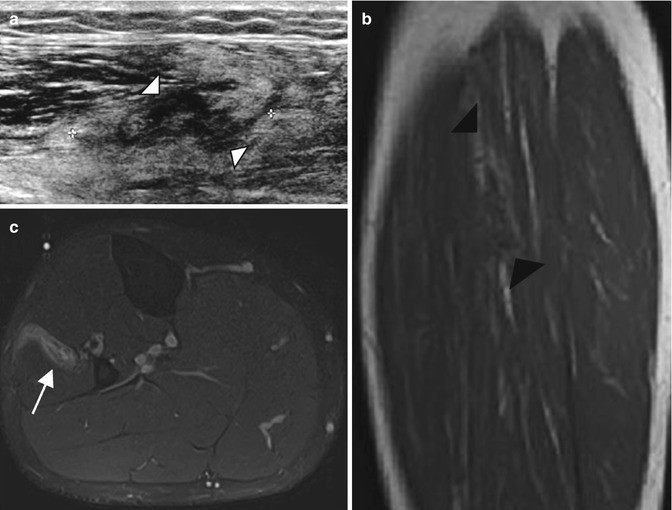

Five-year-old girl with intramuscular venous malformation. (a) Ultrasound image. (b) Ultrasound image after local compression. (c) Color Doppler image. (a) Ultrasound image shows a heterogeneous lesion (arrowhead) with internal fluid component (arrow). (b) The lesion is compressible (arrowhead). (c) After decompression, filling of the cavities (vessels) can be observed on color Doppler US

Intramuscular venous malformation of the thigh in a 32-year-old man with pain exacerbated during exercise. (a) Ultrasound. (b) Sagittal T1-weighted MR image. (c) Axial T1-weighted MR image after Gadolinium contrast administration, with fat suppression (a) Ultrasound shows a nonspecific intramuscular soft tissue lesion (white arrowhead) (b) MR image demonstrates fat component surrounding the lesion (black arrowheads), (c) and serpiginous enhancement after gadolinium contrast administration (arrow)